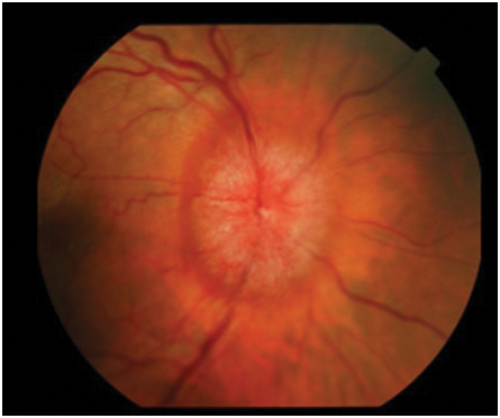

Figure 2: Optic disc photograph showing blurring of all disc margins

with some haemorrhages at upper and lower poles.

The clinical appearance of the optic disc in papilloedema must conform with the progressive changes noted in the last paragraph, so that the first part of the disc to show swelling must be where the nerve axons from the retina are most numerous, that is at the upper and lower poles. Here the fibres from the temporal retina arching around the papillomacular bundle enter the limited space at the six and 12 o’clock positions, limited because the nasal retinal axons are occupying a large portion of the nasal portion of the disc and the papillomacular bundle the temporal portion. Thus the place to look for early papilloedema is at the upper and lower poles (Figure 1) and not, as stated in many textbooks, on the nasal side nor in the cup or blood vessels which will only be involved later. As papilloedema progresses all the margins and the disc itself will become swollen (Figure 2), then vascular dilatation becomes evident (Figure 3) leading to leakage of fluid (oedema) and later again haemorrhages appear (Figure 4).